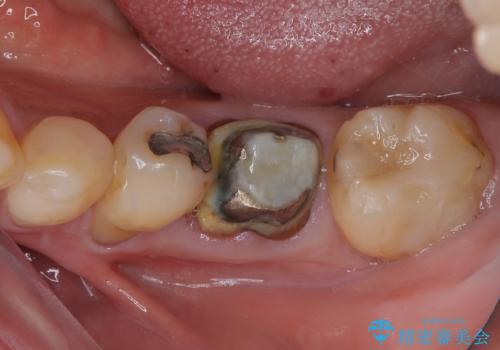

最新の症例